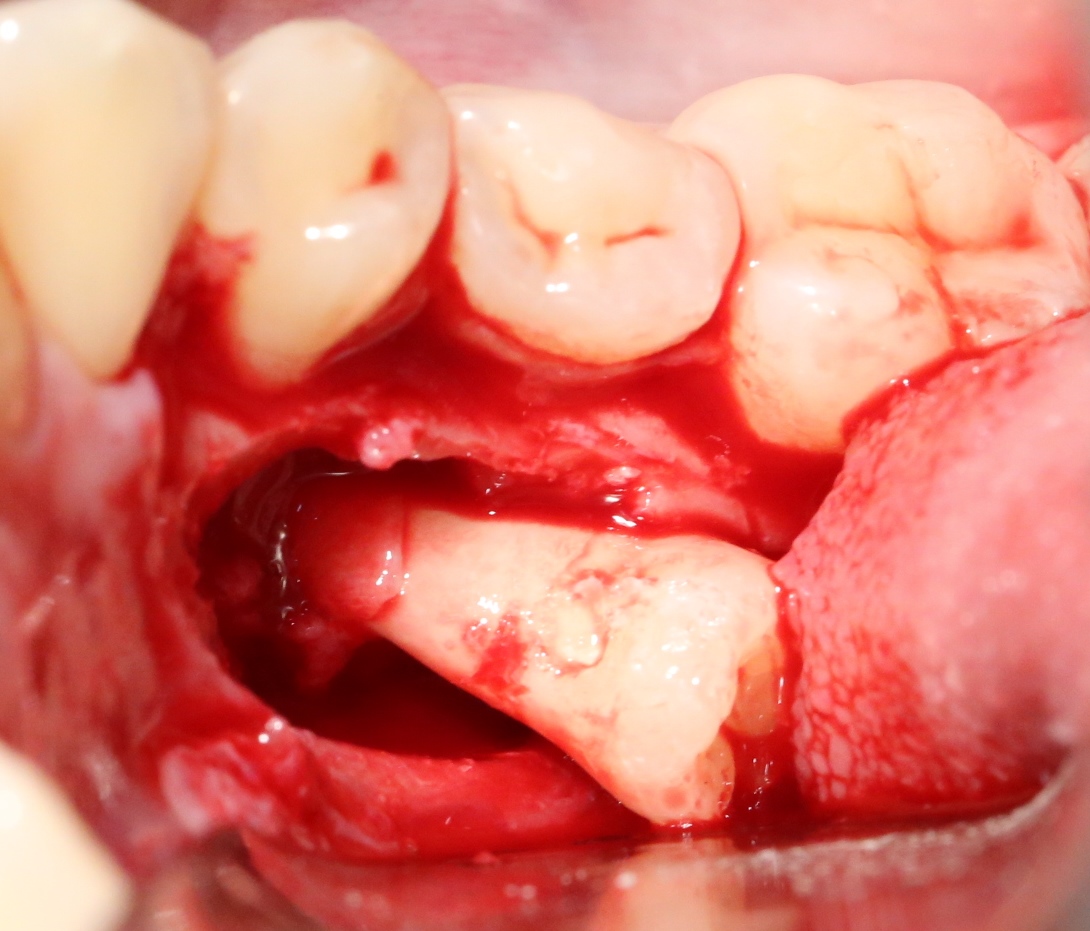

Костная «дверца» на время отделяется и убирается в физраствор, а мы видим следующее:

Это фолликулы и, частично, коронковые части сверхкомплектных зубов.

Теперь аккуратно нам нужно выделить сами зубы:

А вот они! Далее мы руководствуемся главным правилом хирурга-стоматолога:

При удалении зубов нельзя прилагать значительных физических усилий. Если операция идет правильно, зубы должны, вообще, сами вываливаться из лунок.

Однако, наши сверхкомплектные зубы вываливаться не хотят. Потому что их коронки образуют что-то вроде клина, который непросто вытащить через маленькое трепанационное отверстие.

Поэтому мы, всё также, с помощью ультразвука, отпиливаем коронку одного из зубов:

После чего, зубы вываливаются из лунок самостоятельно. В прямом смысле слова:

Вот удаленные зубы:

А вот их лунки: